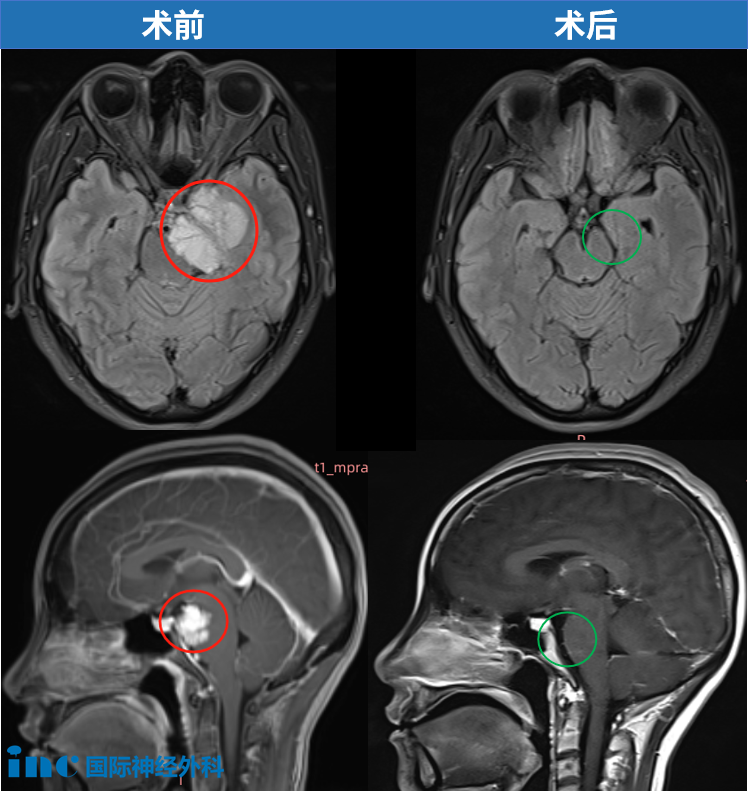

36岁的小宛,也是在一次体检中偶然查出,肿瘤一直没有显现出任何症状,毫无存在感。面对这个“哑炮”,小宛没有过多犹豫就做出决定。在北京天坛医院,福教授为她成功手术——“我在ICU里面呆了4个多小时就出来了,第2天下床,第9天出院。没有剃头发,现在连伤口都长出了头发,完全看不到伤口了。”更为难得的是,术后一个月,小宛几乎恢复如初。点击阅读:天坛医院手术纪实 | 4.5cm脑膜瘤紧压脑干成功手术,勇敢辣妈的彪悍人生!